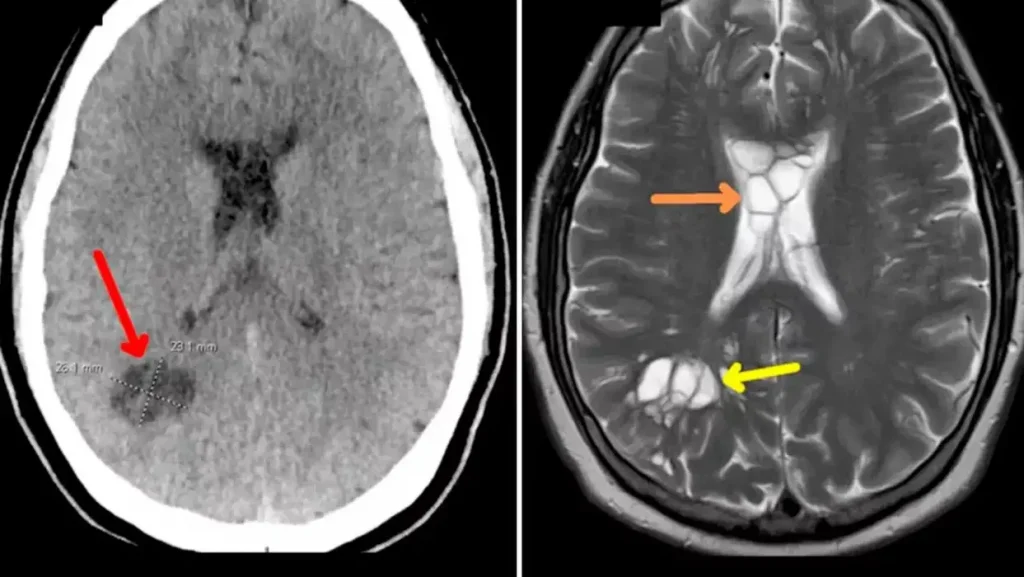

Nakon što je mjesecima trpio migrene, muškarac je otišao kod doktora koji ga hitno poslao na snimanje glave. Na snimanju se ispostavilo kako je crv položio jaja u njegov mozak i iritirao tkivo ispod njegove lubanje.

Liječnici vjeruju da je parazit ušao u njegovo tijelo nakon što je konzumirao nedovoljno pečenu slaninu i putovao iz crijeva u mozak kroz krvotok.